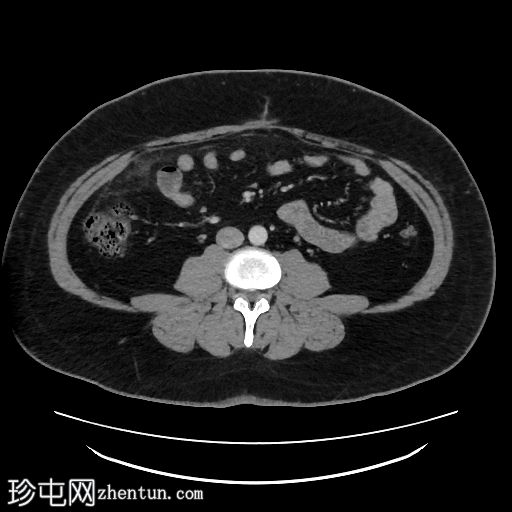

轴向C+门静脉期

肝脏脂肪变性,伴地图样脂肪沉积。胆囊扩张,胆囊壁增厚,周围浑浊,胆囊颈结石,胆囊前壁凹陷(胆底张力征)。

本病例展示了CT扫描在急性胆囊炎(通常是意外诊断)诊断中的价值。CT扫描通常比

检查更具评估价值,因为能够更准确地识别脂肪条带。胆囊底张力征提示胆囊受阻并承受压力,因为它会凹陷(而不是顺应)前腹壁。